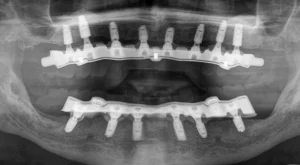

This gentleman felt that he had let his mouth go and was ready to get them sorted out. Even though he had most of his teeth, they were heavily decayed, abscessed, split and loose. Regrettably, his upper and lower teeth were past saving and were removed.

We placed eight upper jaw and six lower jaw implants. These were then joined with a bar.

Below left, you can see the inside of his denture with the metal sleeve that fits onto the bar. The custom-made bar is pictured on the right. Although the bars look different initially, patients love the bar’s stability for their dentures. The dentures are simple to remove and place. There’s no movement on eating, and cleaning and maintaining the implants long-term is easier.